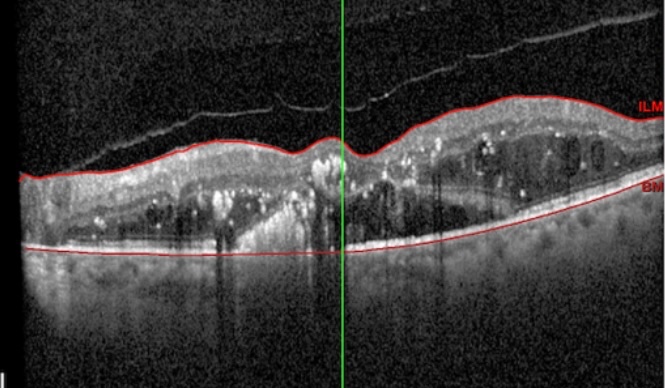

Tipos de edema macular en OCT

Difuso: Engrosamiento homogéneo. Común en etapas tempranas.

Quístico: Espacios hipo-reflectivos intrarretinianos. Asociado a fuga capilar crónica.

Seroso: Desprendimiento del neuroepitelio. Suele acompañar isquemia severa.

Traccional: Elevación irregular de la retina por tracción vítrea. Puede requerir cirugía.